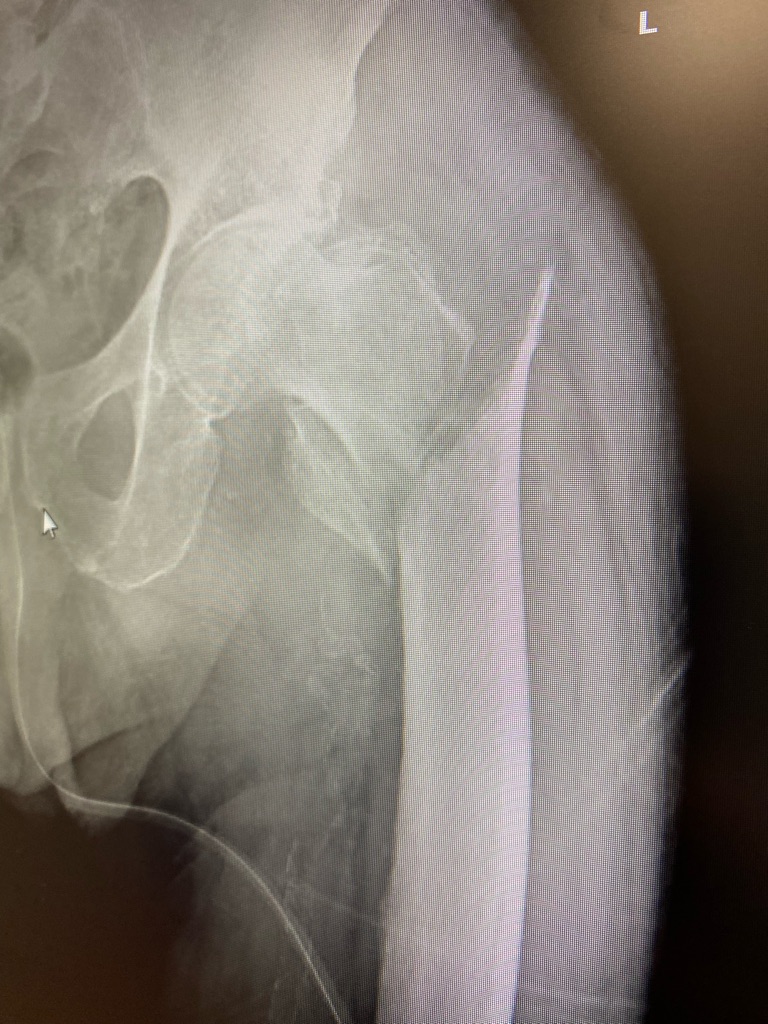

Super terrible femor break.